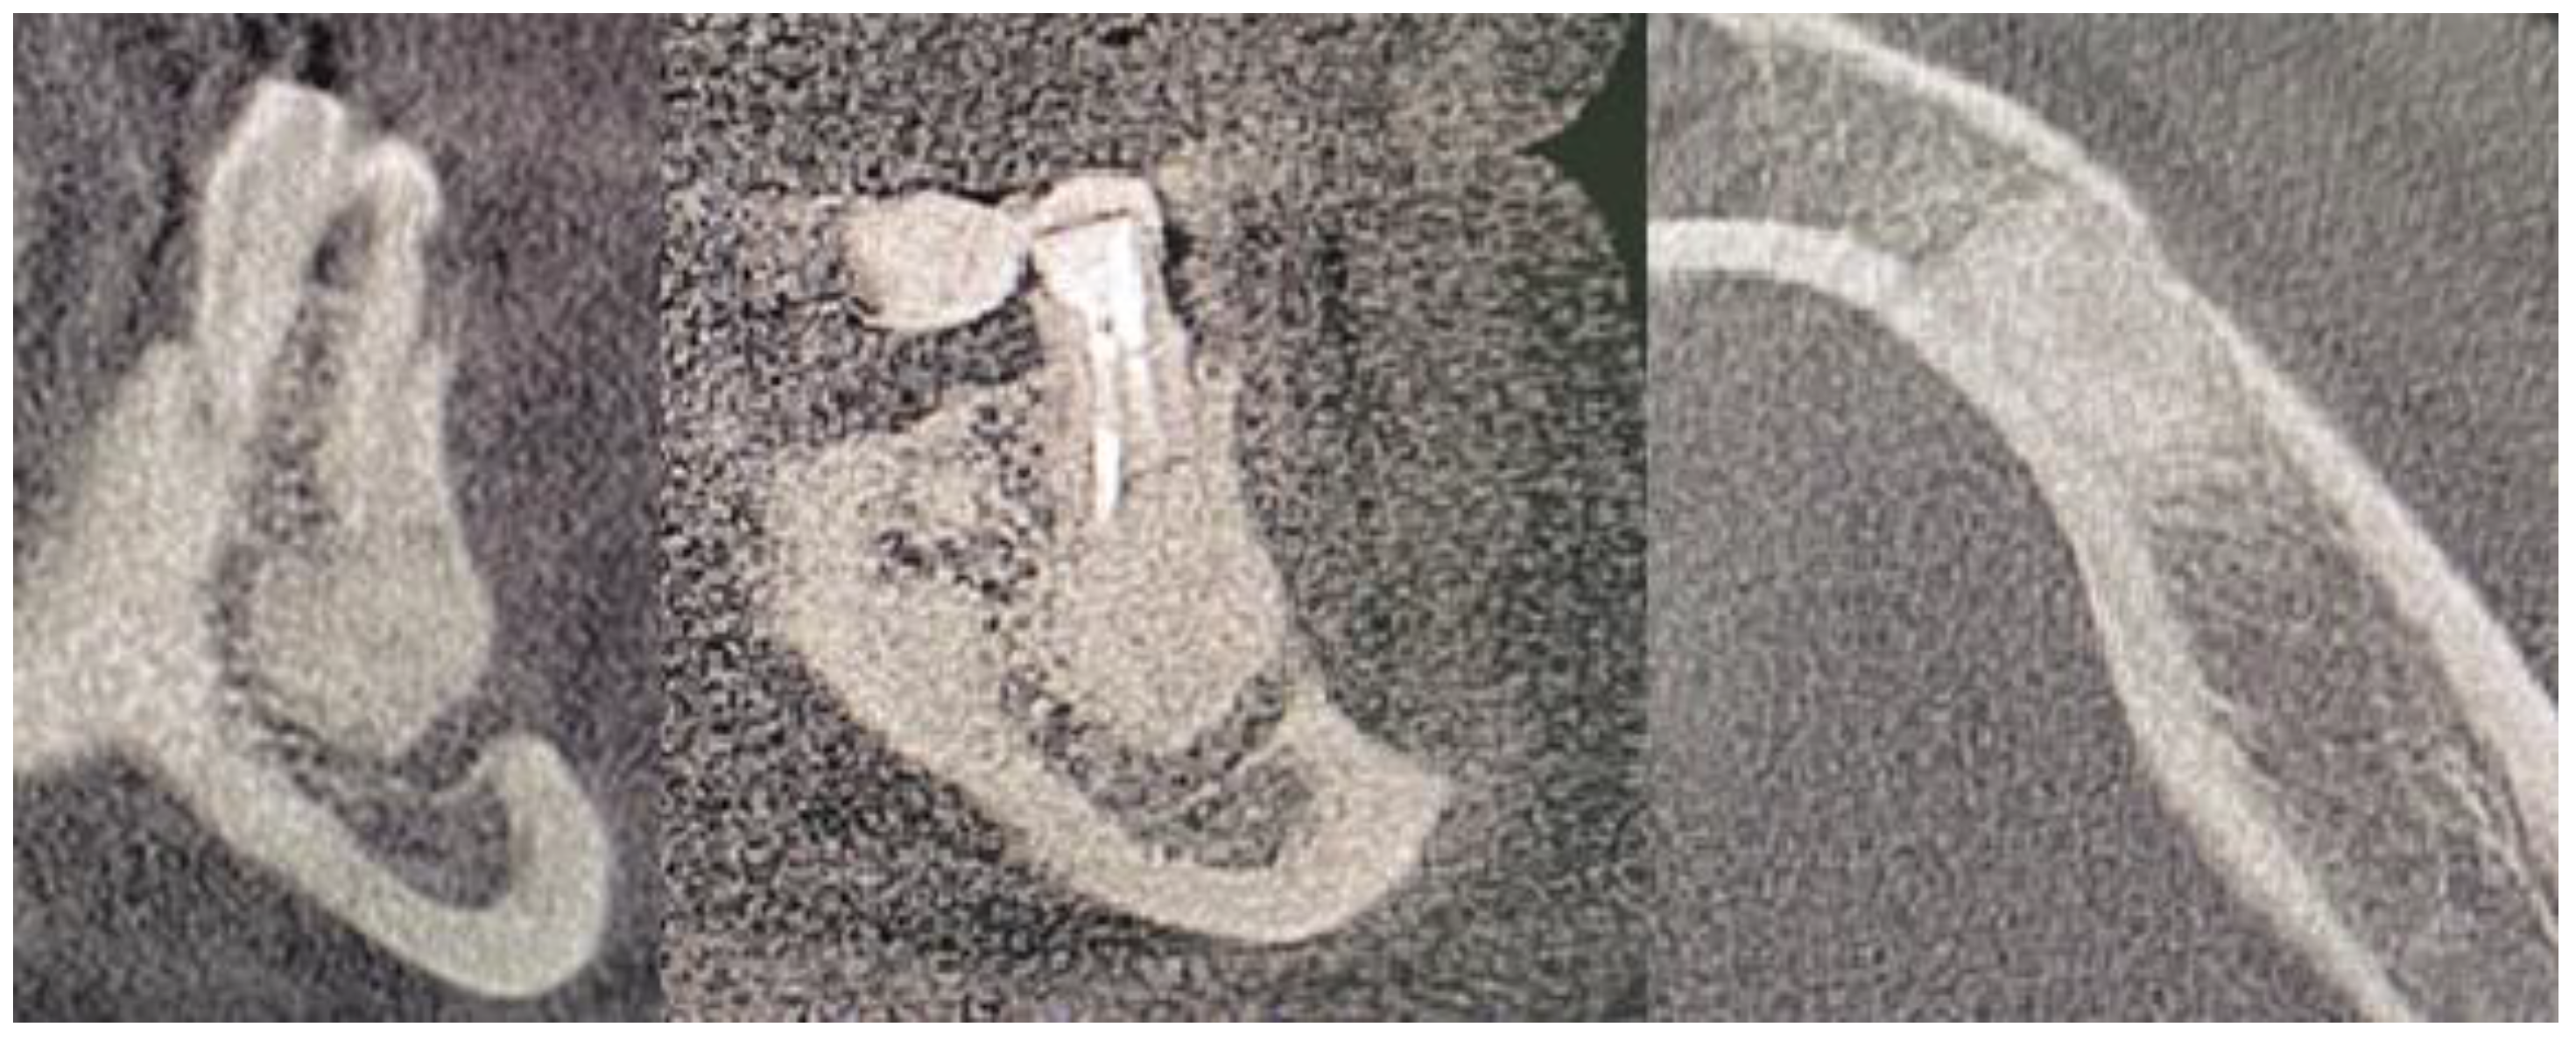

2. Case Description

- A close CBCT evaluation before surgery;